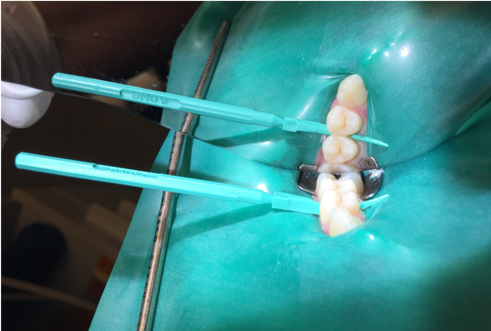

A 28-year-old woman, who previously had braces, had circumferential gumline decalcification (Figure 1) and wished to arrest lesions before they worsened (bitewing, Figure 2). The following protocol is consistent with the product instructions for the resin infiltration material from DMG America, which is the only commercially available resin infiltration system in the US.

3. Place a rubber dam. Local anesthetic is not necessary, but topical anesthetic may be helpful for patients who find the clamp to be uncomfortable.

Fig 2.  Circumferential gumline decalcification (Fig 1) and bitewing (Fig 2) of a 28-year-old woman.

Figure 2